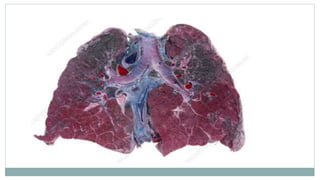

ASBESTOSIS

 It is know as “diffused pulmonary fibrosis”

which is caused by inhalation of asbestos

fibers.

 The presence of asbestos in the lungs

eventually causes scarring or “fibrosis” which

may later result in the formation of tumors and

the development of cancer.